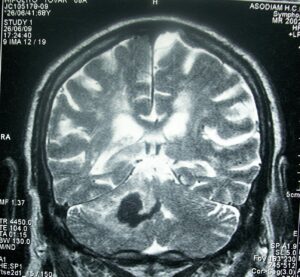

Brain herniation MRI.

Brain herniation.